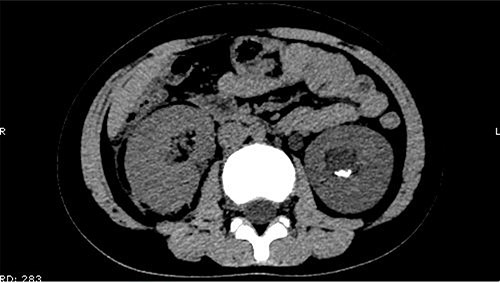

The patient was confined to bed, fasted and prescribed a daily intravenous infusion of cefazolin sodium pentahydrate, 2.0 g for 10 days. CT showed some irregular high-density shadows were present in the left renal pelvis (Fig. 1), and a small strip of high-density shadow was apparent in the bladder cavity (Fig. 2). Blood tests showed no abnormality in serum calcium concentration. Cefazolin sodium pentahydrate was discontinued immediately.

Some irregular high-density shadows was present in the left renal pelvis.